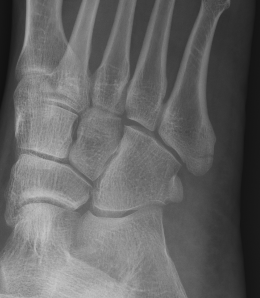

Os peroneum

Location

Sesamoid in peroneus longus

- at level calcaneo-cuboid joint

- articulates with cuboid